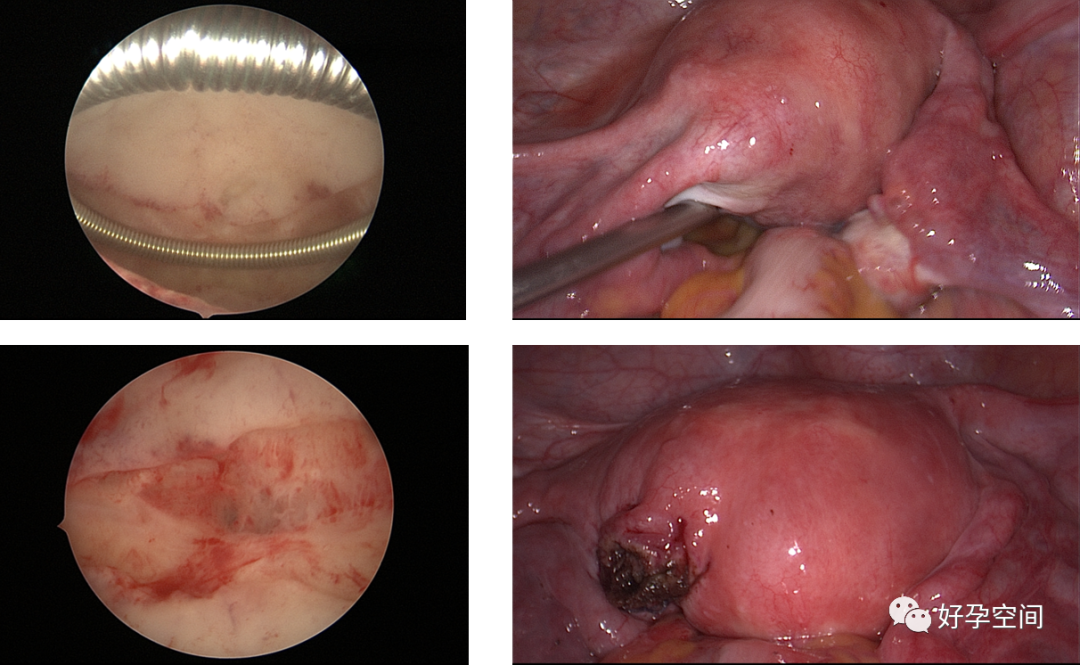

4、取胚、人流及药流不全、带环受孕、切口妊娠、宫角妊娠、切口憩室、宫颈妊娠,胎盘残留、胎盘粘连、胎盘植入、子宫动静脉瘘手术。

胚物残留、左侧宫角妊娠、切口妊娠、切口憩室

胎盘残留、胎盘粘连、胎盘植入、动静脉瘘

7、最近有专家在研究宫腔镜下的缝合技术。

宫腔镜下缝合固定曼月乐环